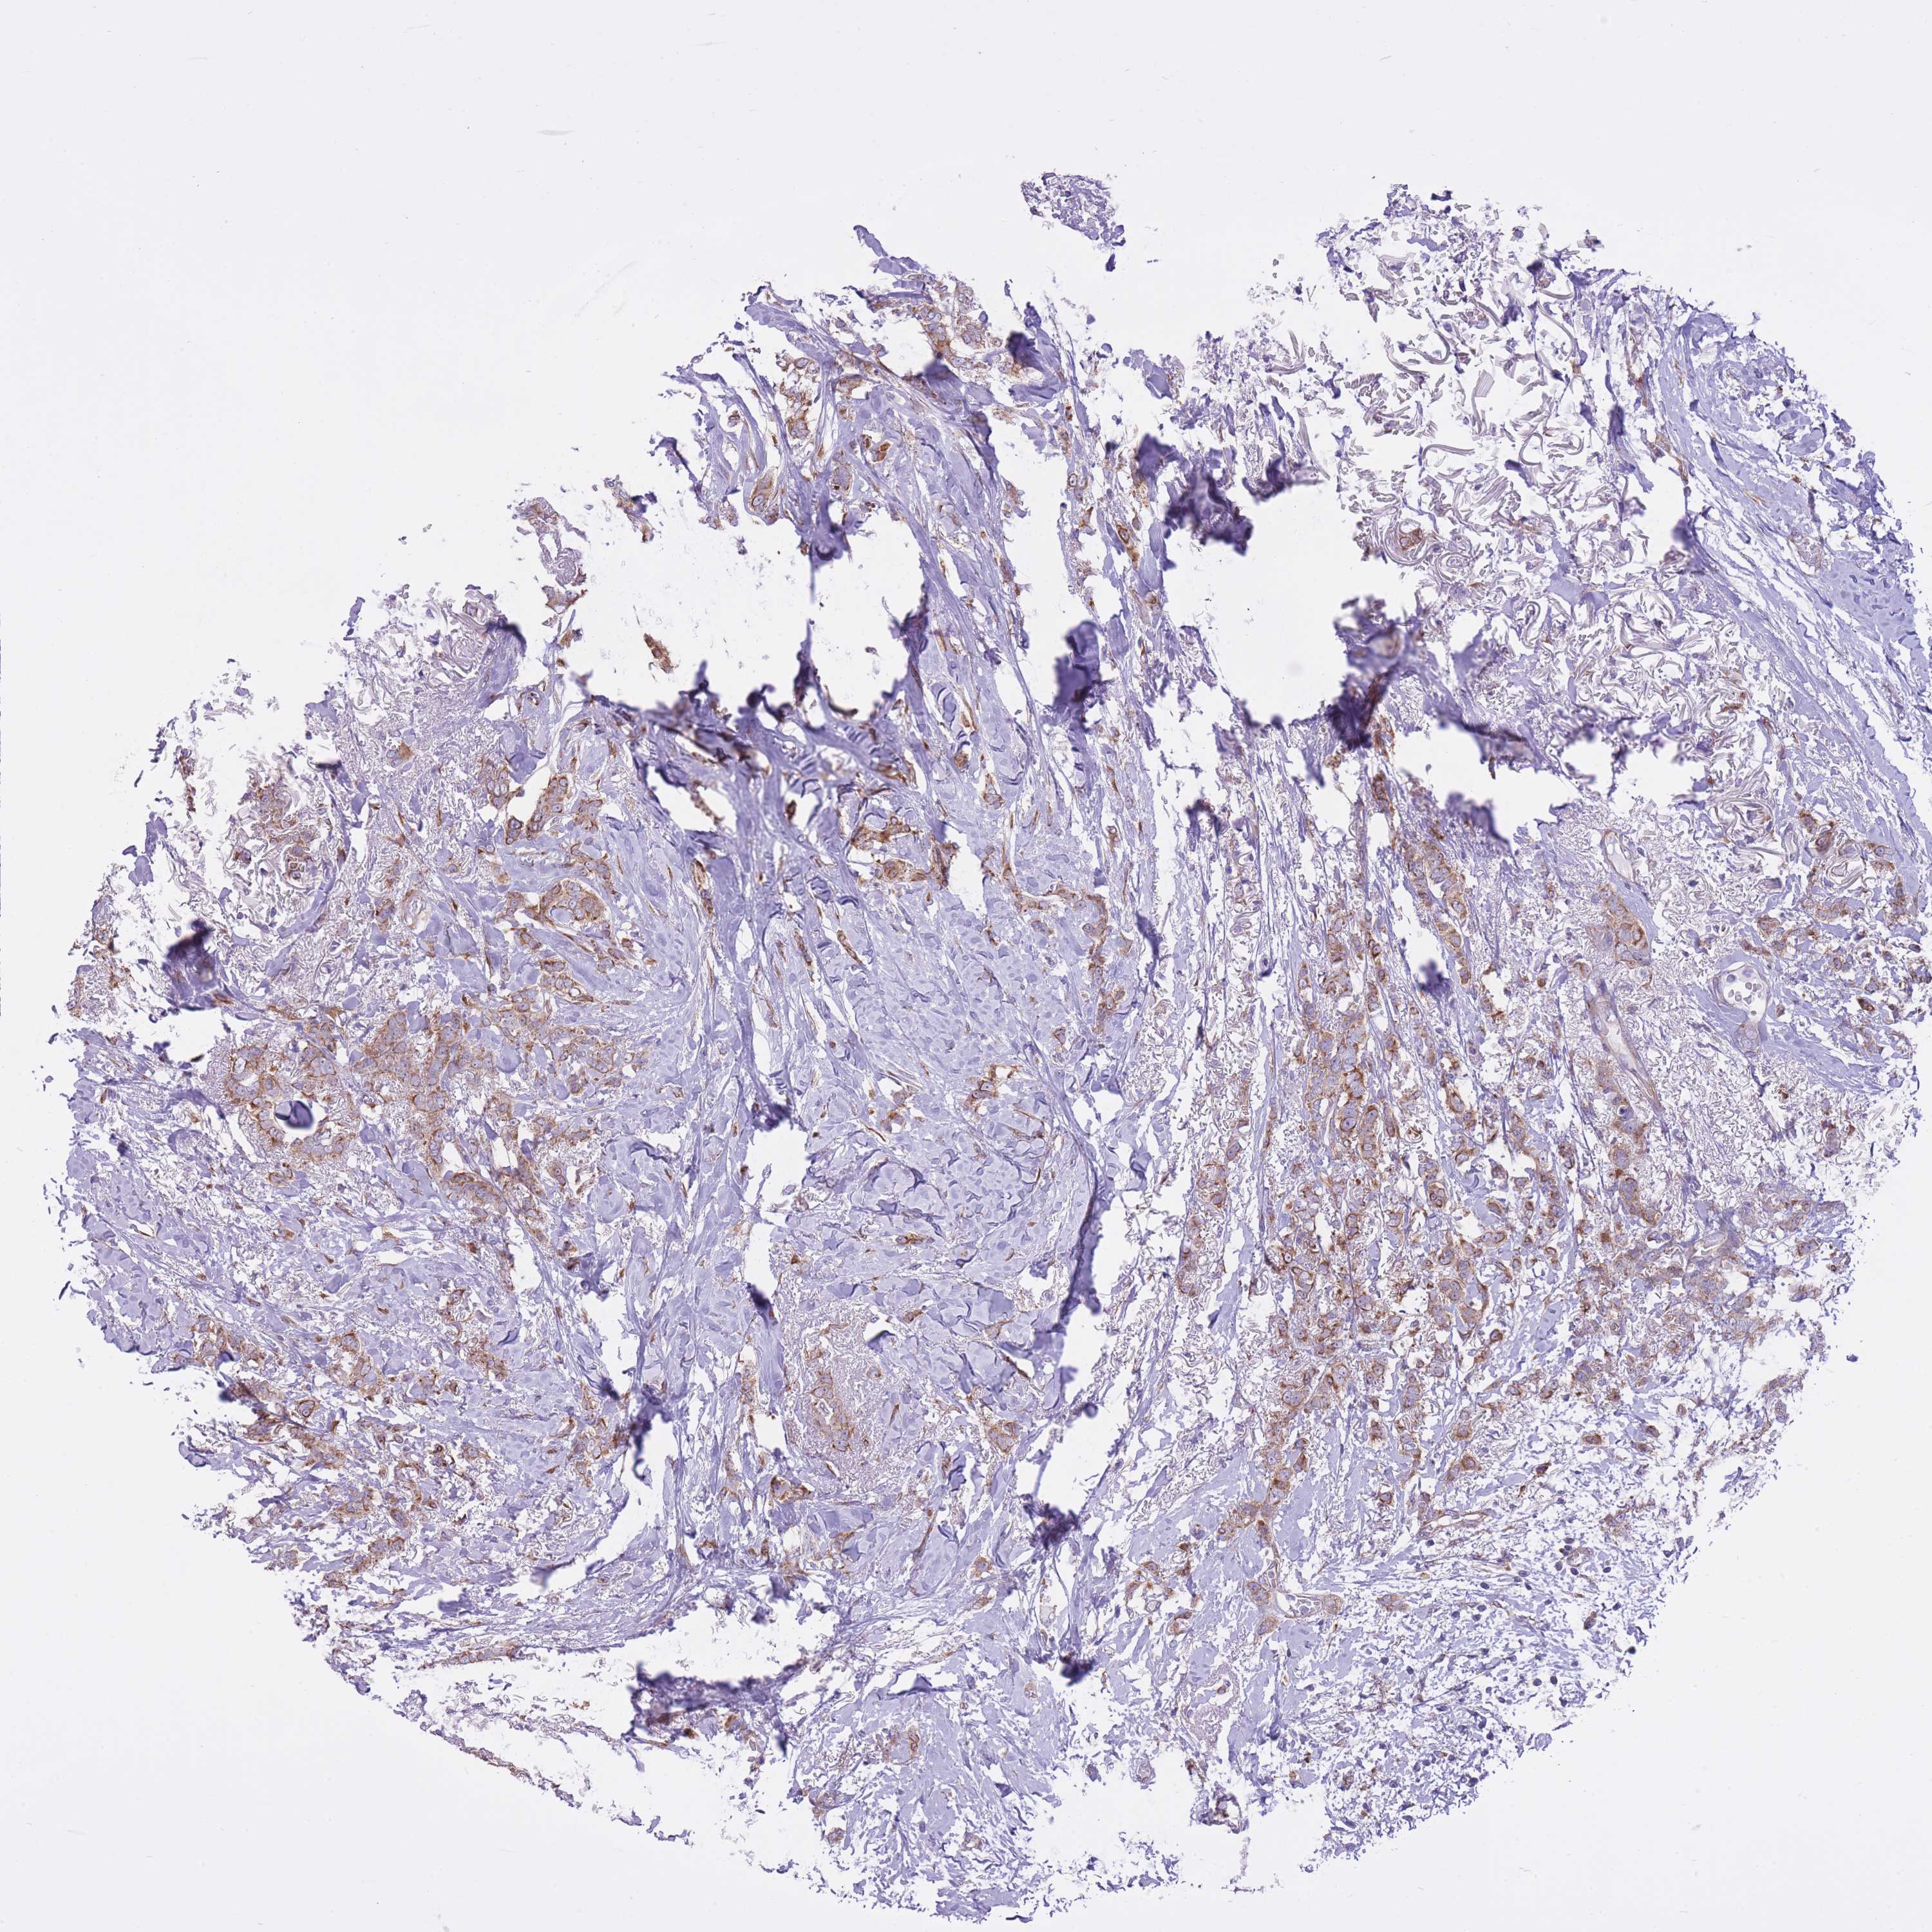

BRCA TCGA BRCA VALIDATION PROTEIN EXPRESSION

ANTIBODIES

AND

VALIDATION